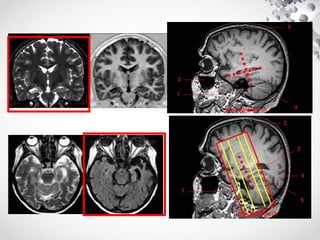

Orientação de Cortes Coronais

PLANOS:

SAGITAL - TOMA-SE POR REFERÊNCIA UMA LINHA QUE ACOMPANHA A PARTE

POSTERIOR DA PONTE (LINHA TRACEJADA)

AXIAL - TOMA-SE POR REFERÊNCIA UMA LINHA QUE ACOMPANHA A LINHA MÉDIA DO

ENCÉFALO OU FOICE CEREBRAL (LINHA TRACEJADA)

CORONAL - SUA IMAGEM REFERÊNCIA (FOV) OBSERVAR SE TOA ANATOMIA ESTÁ

DENTRO DO MESMO

Cortes Coronais

Orientação de Cortes Axiais

Orientação de Cortes Sagitais

PARA ORIENTAR A AQUISIÇÃO NO PLANO SAGITAL TOMAREMOS POR

ORIENTAÇÃO A LINHA MÉDIA DO ENCÉFALO